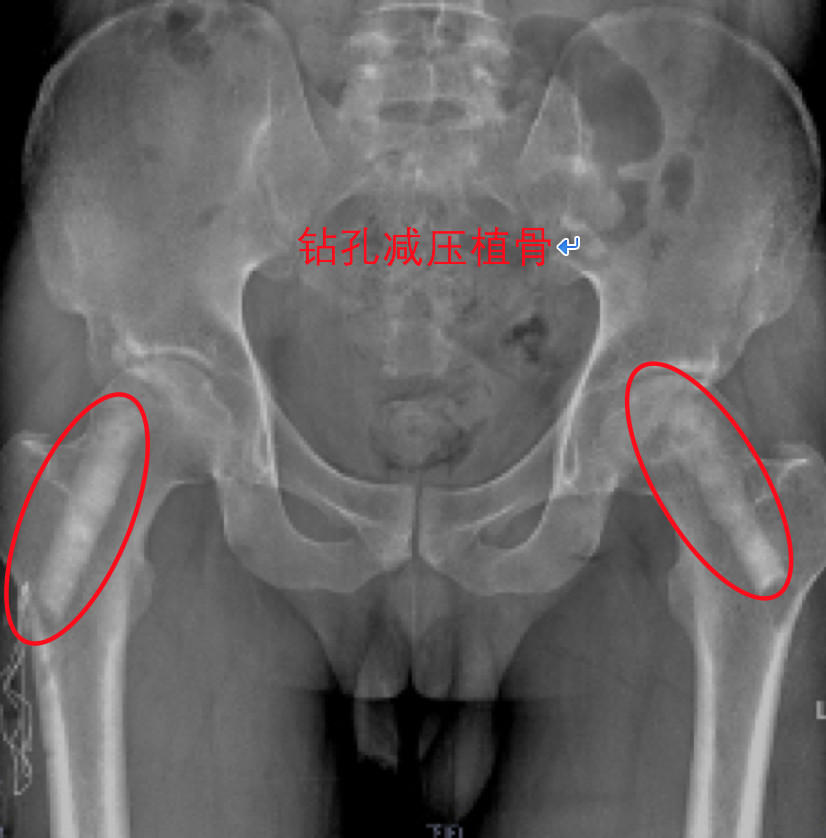

钻孔植骨术:比微创钻孔减压术稍大的手术,钻孔直径10-20mm,通过孔道清除死骨,植入自体骨或人工骨。